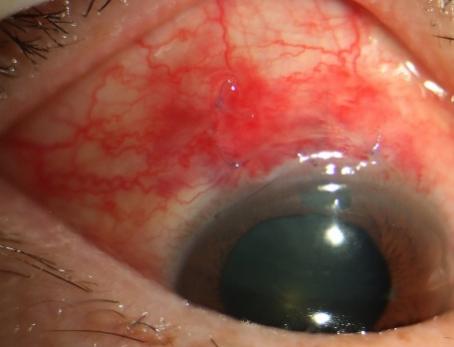

安徽省蚌埠市60岁的张阿姨在前往兰州的火车上突发右眼胀痛、视物模糊,还伴有头晕、恶心、呕吐等症状。休息后这些症状并未缓解,张阿姨在西安站下车后立即被送至我院急诊科就诊。急诊科医生考虑到症状可能与眼部疾病有关,遂请眼科医生会诊。经眼科医生仔细检查后发现,张阿姨右眼视力仅为指数,眼压高达75mmHg(正常眼压范围为10-21mmHg),角膜上皮弥漫性雾状水肿,前房极浅,瞳孔欠圆,直径约6mm,晶状体混浊。诊断为张阿姨是原发性急性闭角型青光眼,即右眼急性发作期、左眼临床前期,双眼老年性白内障。张阿姨随即被收住眼科病区,接受局部及全身降眼压药物治疗,效果不佳。考虑到持续高眼压对视神经的损伤,眼科范雅稚副主任当机立断为患者进行前房穿刺放液,眼压暂时得到有效控制。但经过一周的治疗及观察后,她的角膜始终未恢复透明,角膜内皮皱褶严重。

随后进一步的辅助检查发现张阿姨的眼部情况极为复杂,双眼小眼球的结构使得眼部的房水循环存在一定障碍,右眼前房深度仅1.27mm,左眼前房深度1.67mm,前房极浅的状况进一步阻碍了房水的正常流通,是引发眼压升高的重要因素之一。同时,张阿姨右眼还存在睫状体脱离的问题,这不仅影响了眼部的正常生理功能,还增加了治疗的难度。她的中央角膜处于灰白水肿状态,角膜不透明这一情况使得内路微创手术及白内障手术无法实施,医生难以清晰观察眼内结构,手术风险会大幅增加。如果不立刻手术,等待角膜恢复透明的过程中,患者又随时可能出现二次青光眼大发作的情况。

针对这一治疗困境,青光眼团队王建明主任、范雅稚副主任及王艳芬博士的深入讨论和分析,结合张阿姨的具体病情,最终决定为她实施单步隧道法---新型微创小梁切除术(SIGS)。这种术式以最小创伤实现高效降眼压,切口小、创伤小,能最大程度减少对眼部组织的损伤,降低并发症发生的风险,且该手术没有额外的一次性耗材,减轻了患者的经济负担,是当下挽救张阿姨视功能的理想选择。实施SIGS手术后第一天,张阿姨右眼眼压12mmHg,角膜基本透明,内皮皱褶明显减少,视力显著提升。术后张阿姨表示没有任何不适感,对治疗效果赞不绝口,并表示等角膜恢复后,一定还要请范雅稚医生亲自为她做后续的手术。由于手术非常微创、安全,张阿姨当天下午就踏上了回安徽的火车。范雅稚副主任介绍:“对于像张阿姨这样角膜条件差、病情复杂、又担心传统小梁切除术并发症的患者,切口小、创伤小、安全性高的SIGS无疑是一个理想的选择,同时也为后续微创手术提供了时间窗。”

术后第一天,未使用缩瞳药物及任何降眼压药物